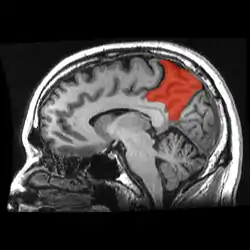

Sagittal MRI slice with the precuneus shown in red. (Anterior to the left.)

In neuroanatomy, the precuneus is the portion of the superior parietal lobule on the medial surface of each brain hemisphere. It is located in front of the cuneus (the upper portion of the occipital lobe). The precuneus is bounded in front by the marginal branch of the cingulate sulcus, at the rear by the parieto-occipital sulcus, and underneath by the subparietal sulcus. It is involved with episodic memory, visuospatial processing, reflections upon self, and aspects of consciousness.